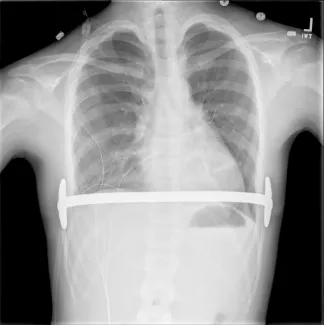

Repair with a metal pectus bar, called the Nuss Procedure, is achieved by bending a stainless bar to fit the chest wall. The bar is then inserted and secured through a small incision under each arm using the aid of a endoscope to monitor and avoid injury to the heart during insertion. The bar goes over the ribs and under the sternum, to push the sternum forward into the new position. The ends of the bar are secured to the chest wall. This procedure takes between 1–2 hours.

Preoperatively, your insurance carrier may require a CT scan to measure the Pectus Severity Index (PSI, also known as the Haller Index), which is the the ratio of the width of the chest wall to the depth at the deepest point of the deformity. This value usually must exceed 3.2 to be considered severe enough to be surgically corrected.

- Sports may be resumed as soon as the surgeon determines this is safe. Some contact sports may be not be permitted while the bar is in place. The bar may prevent adequate chest compressions during CPR and defibrillation requires paddle adjustment to be effective.

- Use of a medical alert bracelet or necklace is recommended at all times in order to notify emergency providers of the presence of a Pectus bar. Recommended bracelet text: Steel bar in chest. CPR more force. Cardioversion ant/post paddle placement.